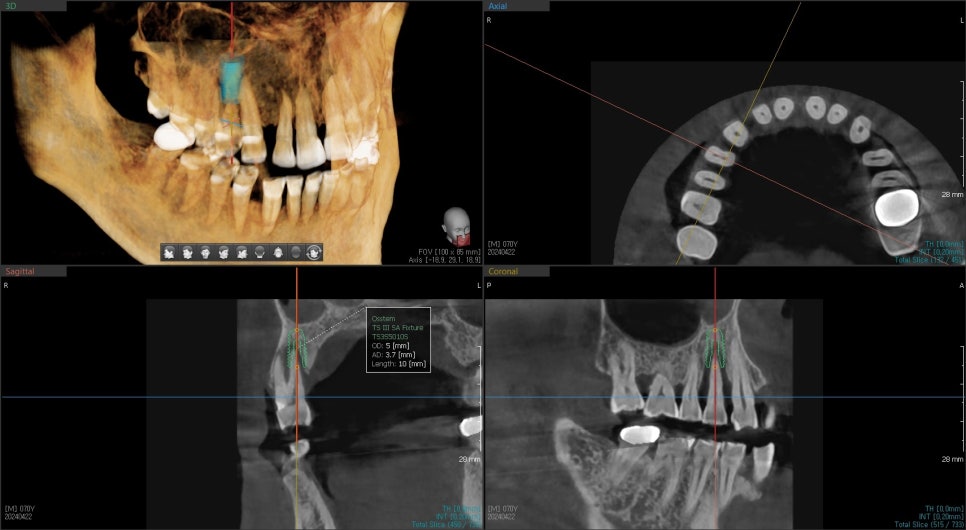

3D CT를 찍어봤더니 역시나 뿌리 주변의

심한 골소실로 인한 동요도로 인한 통증으로 진단하고

환자분께는 치아의 수명이 다해서 더 이상 치료는 불가능하고

발치 후 즉시 임플란트 수술에 대해 설명드렸습니다.

치아가 있던 공간이 컸기 때문에 수술과 동시에

기존 뼈의 볼륨을 유지하기 위해 치조골이식술까지 동시에 진행했습니다.

CT 분석을 토대로 수술 방향을 잡았습니다.

술후 사진을 보면 수술 전 CT를 찍는 것이 얼마나 도움이 되는지 알 수 있는 사진입니다.